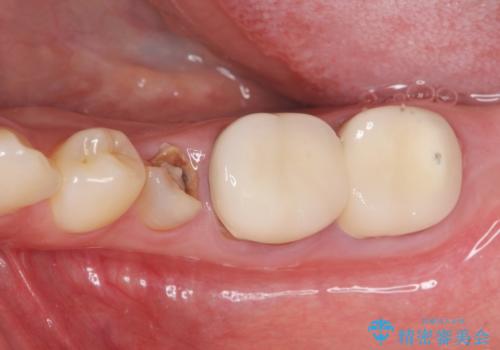

[ 臼歯部インプラント治療 ] 抜けた歯を治療したい

- 抜け落ちた歯と、残った歯の揺れの治療を希望され来院されました。

インプラントを埋入するために

① 不十分な顎骨量 → インプラント埋入と同時に骨の造成

② 角化歯肉の不足 → 遊離歯肉移植術

③ 歯の揺れ → 残存歯の連結補綴

を行う治療計画を立案します。

ただ歯のないところにインプラントを入れて、終わり。と言った治療ではなく、長期的に安定した咬合状態を保てるような噛み合わせの整備や清掃しやすいような歯周環境を整えることで良好な治療結果を得ることができました。